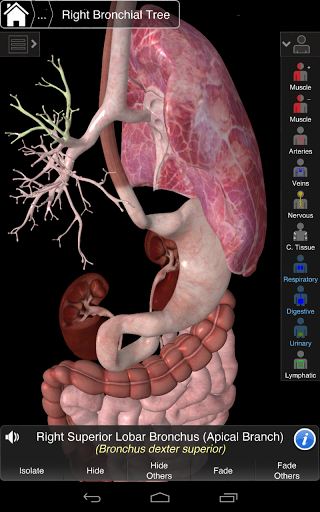

Essential Anatomy 3 represents the latest in groundbreaking 3D technology and innovative design. A cutting edge 3D graphics engine, custom built by 3D4Medical from the ground up, powers a highly-detailed anatomical model and delivers outstanding quality graphics that no other competitor can achieve.

The app represents a unique approach to learning general anatomy. The graphics are unparalleled and make learning, through the use of informative content and innovative features, a rich and engaging experience.

⁃Respiratory

Essential Anatomy 3 is responsive, visually stunning and effortless. The app is fully 3D, meaning that you can view any anatomic structure in isolation, as well as from any angle.

Clever functionality found within the app allows the user to strip away layers of muscle via the ‘scalpel’ tool. This app provides users with the ability to turn on/off systems without the need to deselect individual structures or muddle through a multitude of predefined regional tabs, like other apps.

---- Latin nomenclature for each anatomical structure